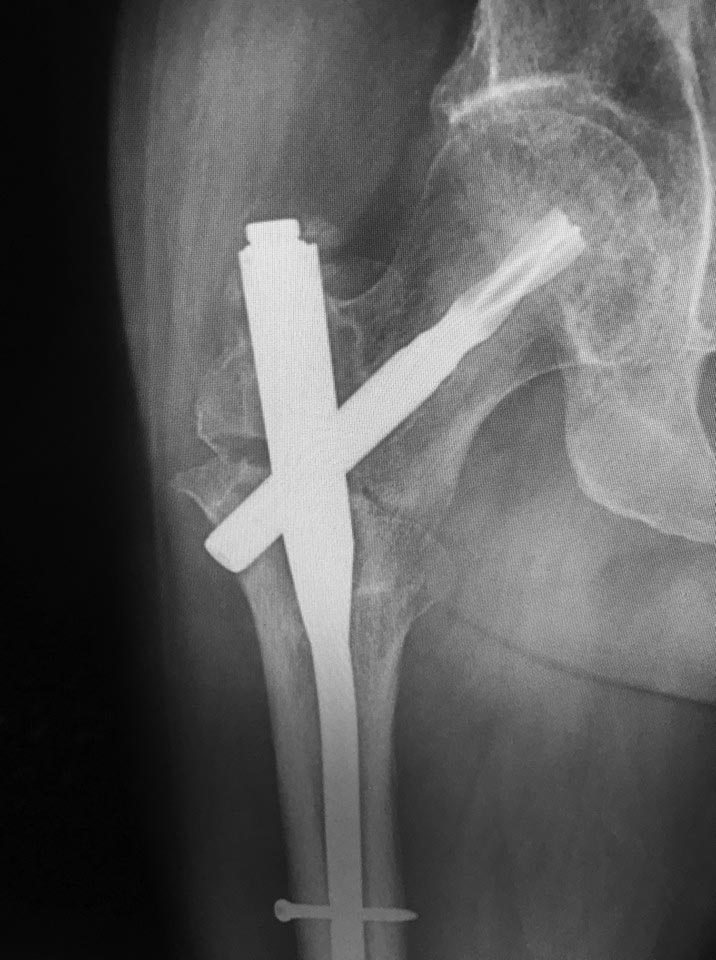

доброго времени суток! как бы вы поступили в данном случае? Пациент 52

года, синтез 7 мес назад, ходьба с костылями.

Боль при ходьбе. Два дистальных блокируемых винта в статике (

срезалось на фото)